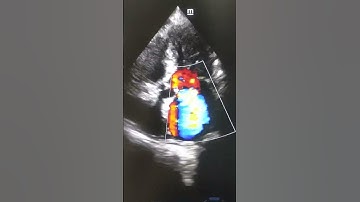

Normal Echo vs Abnormal Echo | Heart Attack | Naresh Rathod #heartattack #humanheart